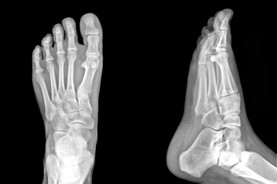

Calgary Foot Doctor & Foot Physio Therapist

The Foot Institute is an association of Calgary Doctors specializing in the medical treatment of the foot and ankle, and is one of the largest groups of foot specialists in Alberta.

The Calgary Foot Institute is dedicated to the medical and surgical treatment of the foot. Our mandate is to provide the best possible medical, surgical and preventative treatment available for our patients. We do this by providing well-trained Doctors who are committed to treat and prevent all types of foot pain, biomechanical disorders, as well as all other problems relating to the feet.

At the Calgary Foot Institute, our Doctors are trained to specifically treat problems associated with your feet or ankles. Below are several of the most common problems that we see on a day to day basis: